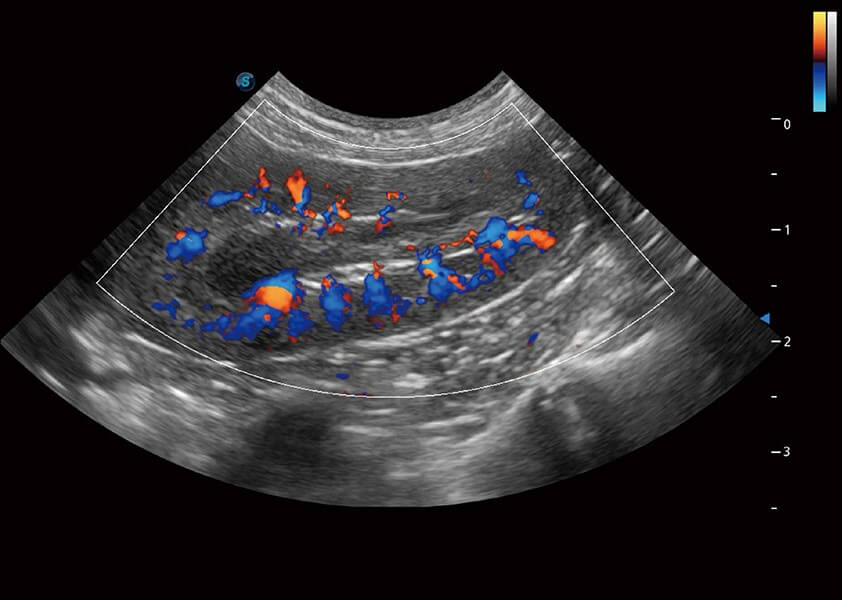

ProPet 60 作为一款高端台式动物超声设备,为动物医生的日常诊断提供了一系列贴合动物临床需求、解决临床实际问题的高级成像功能。凭借全系列高清探头,满足医生对腹部、心脏、生殖、浅表、肌骨等成像的所有需求,切实帮助您提升检查效率,提高诊断信心。

动物是人类最亲密的朋友和最值得信赖的伙伴。银河优越会也一直致力于探索动物专用的超声影像解决方案。 全新推出的ProPet系列,是银河优越会在动物超声影像智能化、专业化、精准化的一次跨越式革新。动物不能用言语来表述自己的不适,通过超声影像,ProPet系列搭建了动物医生与不同物种沟通的“桥梁”,为动物医生注入了“治愈之力”。